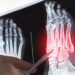

- Kaulų pažeidimai: netikėtas ar stiprus skeleto ir sąnarių skausmas, dažnesni kaulų lūžiai, tirpimas ar silpnumas galūnėse, tinimas.

- Vaizdiniai tyrimai – rentgeno nuotraukos, kaulų skenavimas, kompiuterinė tomografija (KT), magnetinio rezonanso tomografija (MRT), pozitronų emisijos tomografija (PET), ultragarsas.